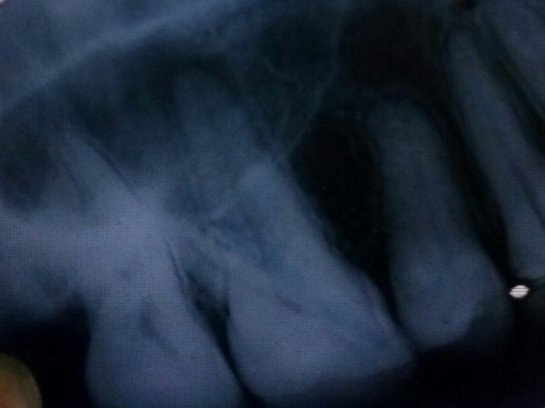

В подростковом возрасте мне сделали резекцию передних зубов из-за кисты. Но спустя примерно 15 лет над зубом образовался, на ощупь, шарик и очень неприятное напряжение под зубом. Я пошла к врачу, он отправил на снимок, но так и не смог мне помочь, и отправил к другому стоматологу, но попасть к нему я так и не смогла.

Вы не могли бы мне сказать, что это? И к кому мне нужно обратиться? У нас городок маленький и специалистов не так много.

У вас так называемый рецидив. Обратитесь к хирургу, думаю, данный зуб придется удалить.